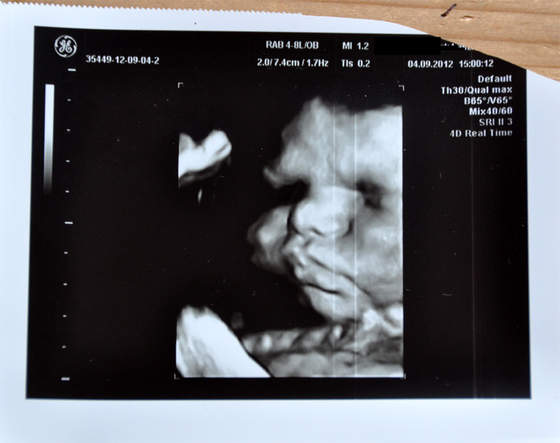

Oto najnowsza fotka Niny